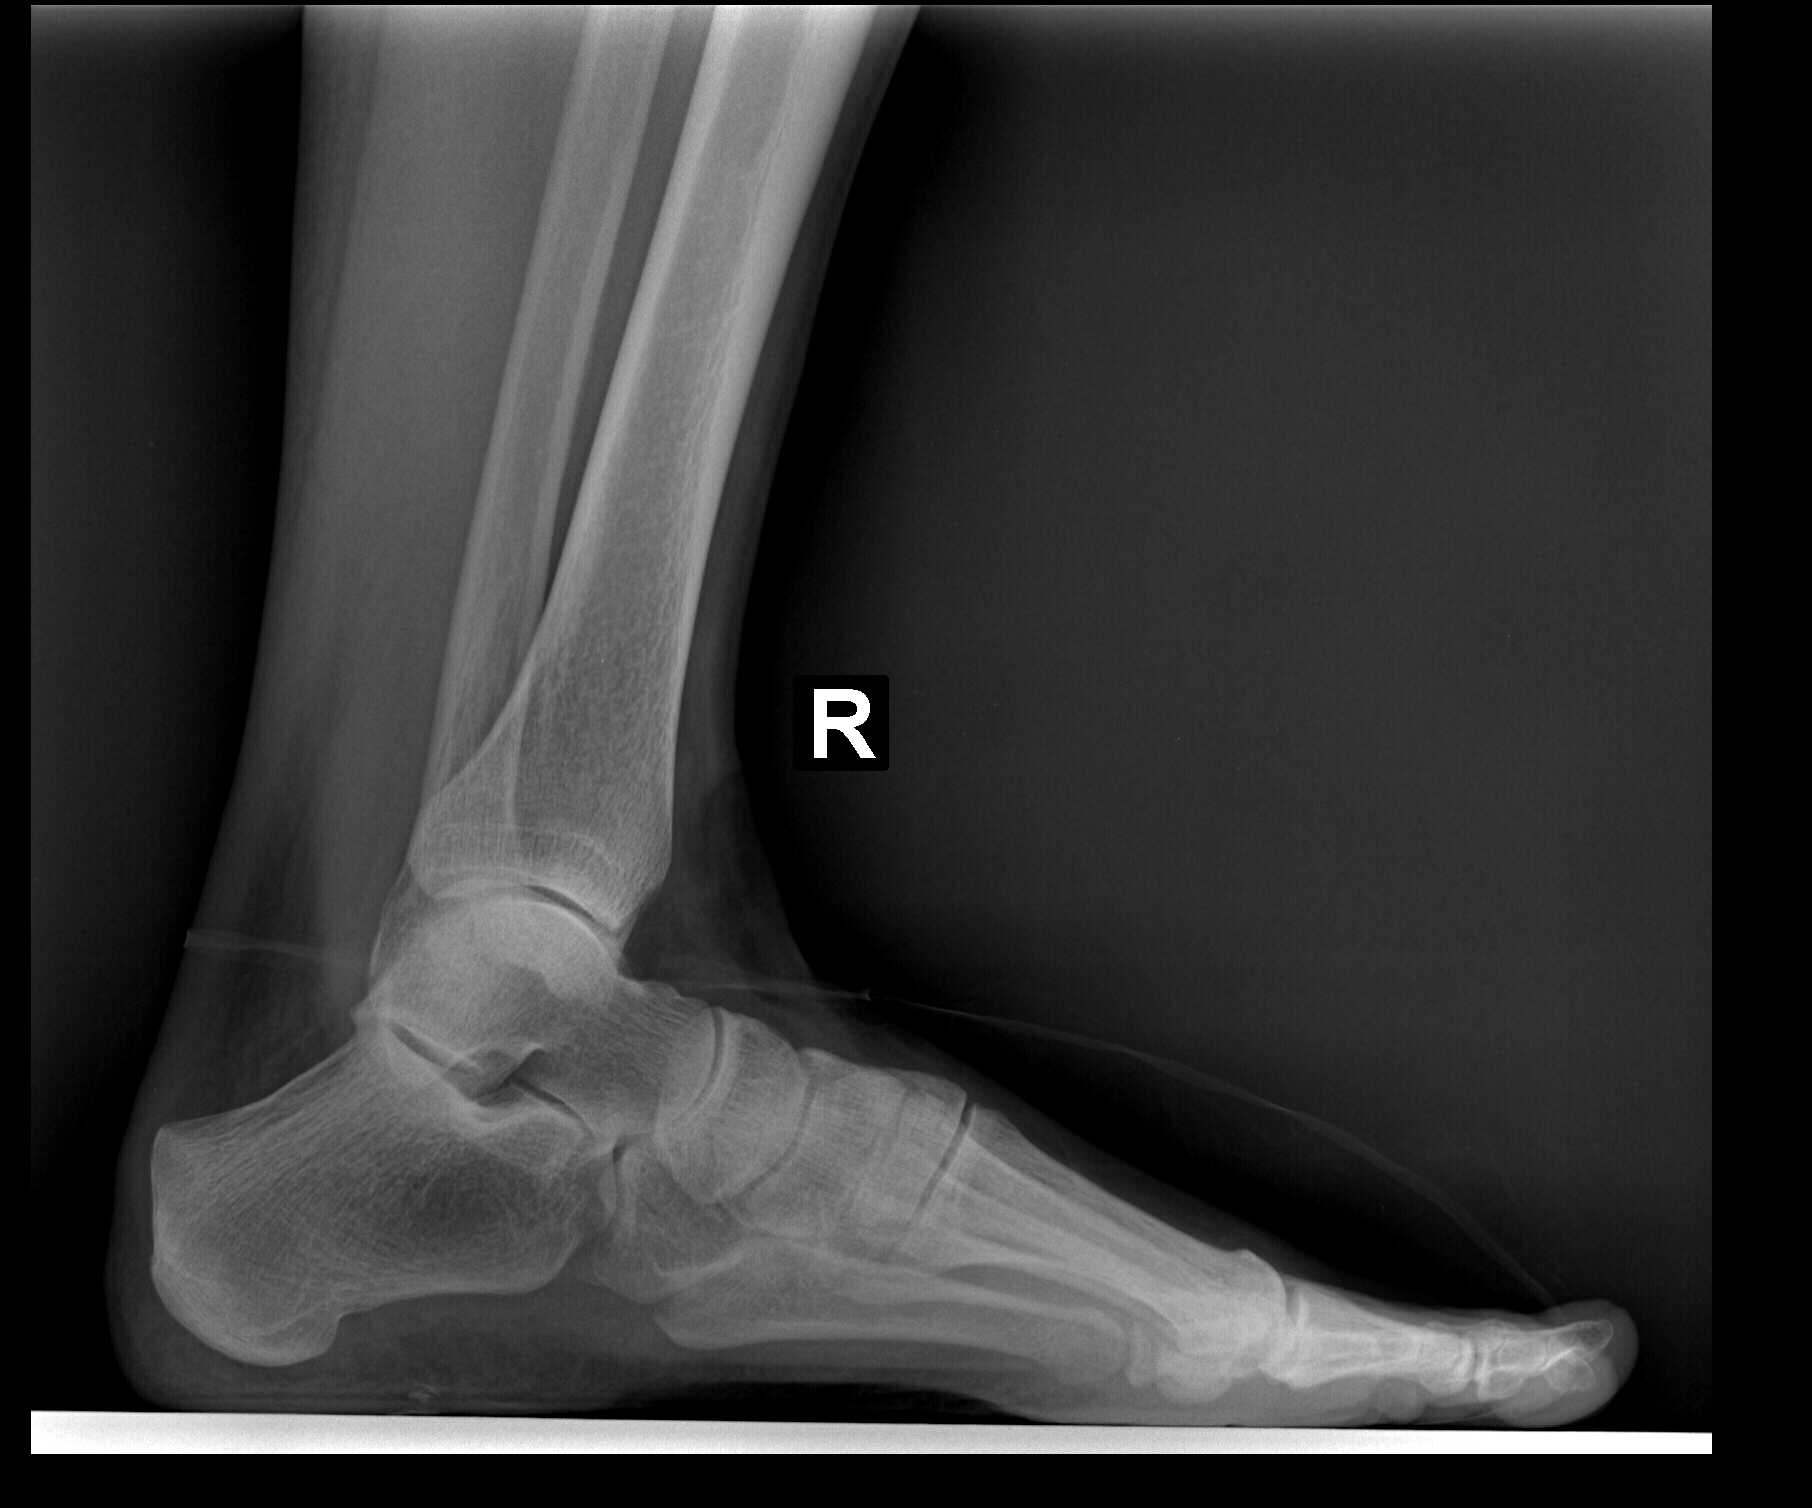

My left foot had healed sufficiently and I then had my pre-surgical appointment with Dr. Gent (see last blog). He is now going to do the same HyProCure Surgery on my right foot. My diagnosis code: 718.37- Recurrent dislocation of joint, ankle and foot; and my Surgical Procedure: 28585 definition: Open treatment of talotarsal joint dislocation, includes internal fixation, when performed.

9:00 am-This surgery went a little faster as Dr. Gent was already familiar with my anatomy and he used the Size 6 HyProCure Stent again just like my left foot. (See this link for Dr. Gent’s video demonstration of a sample stent into his foot skeleton.) I had the same wonderful anesthesiologist, David Bobiak, CRNA from Olympia Anesthesia.